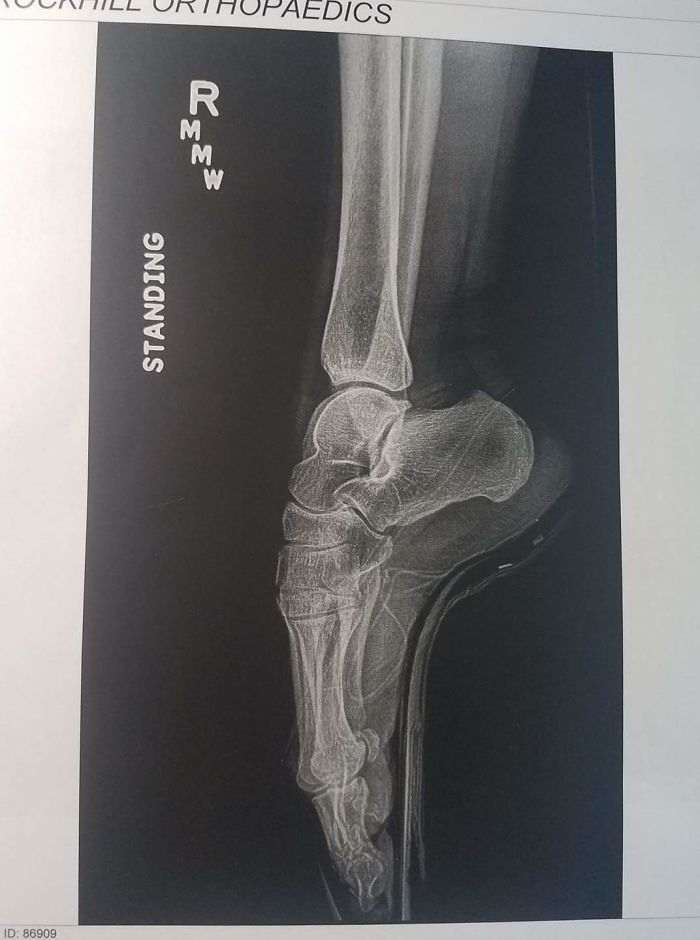

Идеальная ножка балерины в Х-лучах